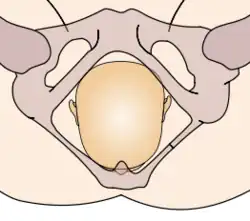

The vertex presentations are further classified according to the position of the occiput, both right, left, or transverse and anterior or posterior:

- Left Occipito-Anterior (LOA), Left Occipito-Posterior (LOP), Left Occipito-Transverse (LOT)

- Right Occipito-Anterior (ROA), Right Occipito-Posterior (ROP), Right Occipito-Transverse (ROT)

The occipito-anterior position is ideal for birth; it means that the baby is lined up so as to fit through the pelvis as easily as possible. The baby is head down, facing the spine, with their back anterior. In this position, the baby's chin is tucked onto their chest, so that the smallest part of their head will be applied to the cervix first. The position is usually "Left Occiput Anterior", or LOA. Occasionally, the baby may be "Right Occiput Anterior", or ROA.[5]